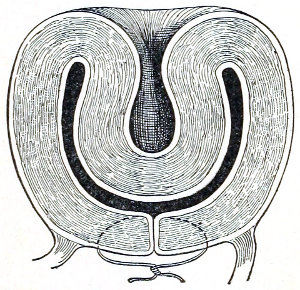

The vagina extends, as a transverse slit in the pelvic floor, upward and backward, approximately in the direction 60 of a line drawn from the ostium vaginæ to the fifth sacral vertebra. It is approximately parallel with the conjugate of the brim, so that when the woman is erect the long axis of the vagina is inclined at an angle of 60° to the horizon. The vagina is not a vertical open tube: it is a slit in the pelvic floor, in health always closed by the accurate apposition of the anterior and posterior walls (Fig. 21). The anterior vaginal wall is about 2½ inches long in a vertical mesial line. The posterior vaginal wall is about 3½ inches long. The vaginal walls are triangular in shape, being broader above than below. The shape of the normal vagina at the pelvic outlet is shown by Fig. 23. The section here shows the vaginal 61 slit of the shape of the letter H. The portions of the slit extending backward and somewhat outward are called the vaginal sulci or furrows. They are directions of diminished resistance in which tears are liable to occur.

Fig. 23.—Section illustrating the characteristic form of the vaginal cleft (Henle): Ua, urethra; Va, vagina; L, levator ani; R, rectum.] 62